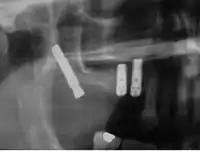

Cigomáticos

Son implantes autorroscantes de longitudes entre 30 a 52,5 mm y una cabeza angulada de 45° que se introducen en el hueso cigomático. Su porcentaje de éxito varía entre 80 y 95 % .Son una alternativa a los injertos de hueso en maxilar atróficos.

Se tratan de implantes más largos que los normales, de manera que estos se anclan a la parte interior del hueso cigomático o hueso de la mejilla. El hueso molar tolera las fuerzas de la masticación, cuando los implantes cigomáticos están conectados a una prótesis dental fija. Se trata por lo tanto de un hueso de buena calidad con un volumen suficiente en todos los pacientes.

Los implantes cigomáticos deben ser colocados por equipos expertos de cirujanos maxilofaciales. Dichos implantes de se colocan bajo anestesia general siempre después de un completo examen quirúrgico y un estudio oral integral completo, que debe incluir modelos dentales del paciente, rayos X y fotos dentales.